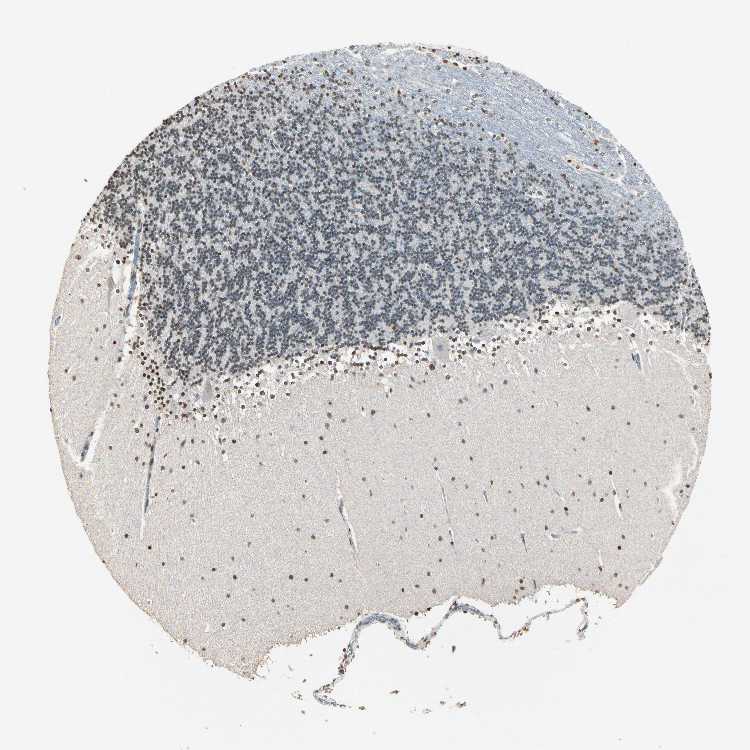

CEREBELLUM - Antibody stainingi

Antibody staining in the annotated cell types in the current human tissue is reported as not detected, low, medium, or high, based on conventional immunohistochemistry profiling in selected tissues. This score is based on the combination of the staining intensity and fraction of stained cells.

Each image is clickable and will lead to virtual microscopy that enables deeper exploration of all samples and also displays staining intensity scores, fraction scores and subcellular localization as well as patient and tissue information for each sample.

Antibody HPA007641Antibody CAB022464

Purkinje cells Not detectedHigh

Cells in granular layer MediumMedium

Cells in molecular layer MediumHigh